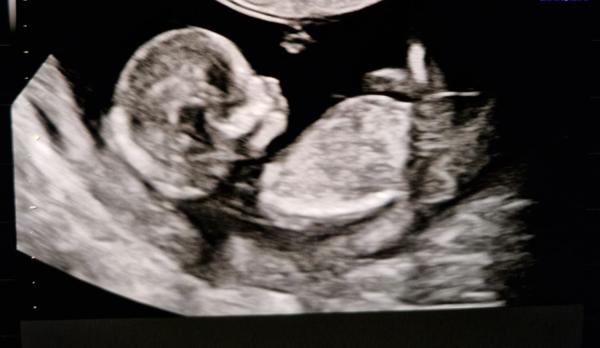

Was bekommt meine Freundin? Junge oder Mädchen?